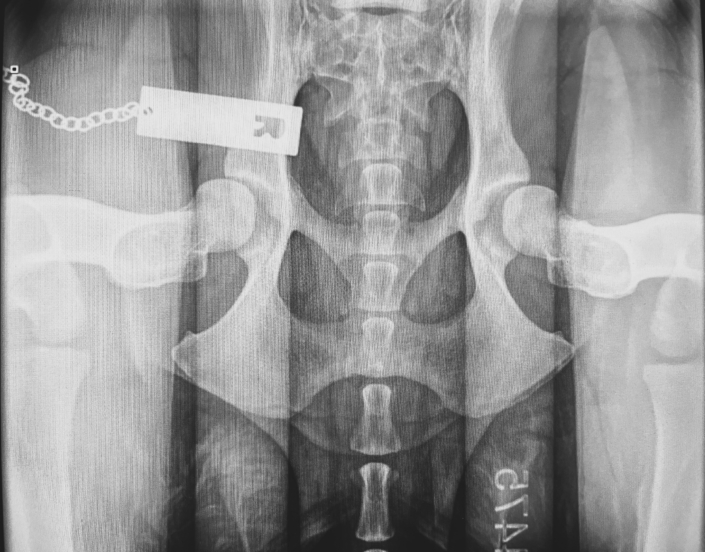

The Hip Extended view, on its own, has poor predictive accuracy for diagnosis of Hip Dysplasia, unless there is radiographic evidence seen (femoral periarticular osteophyte formation, subchondral sclerosis of the craniodorsal acetabulum, osteophytes and joint remodelling). This view actually forces the femoral heads into the acetabulum, therefore masking joint laxity.

- Three (3) radiographs will be taken – a hip extended view, a compressed and distracted view.